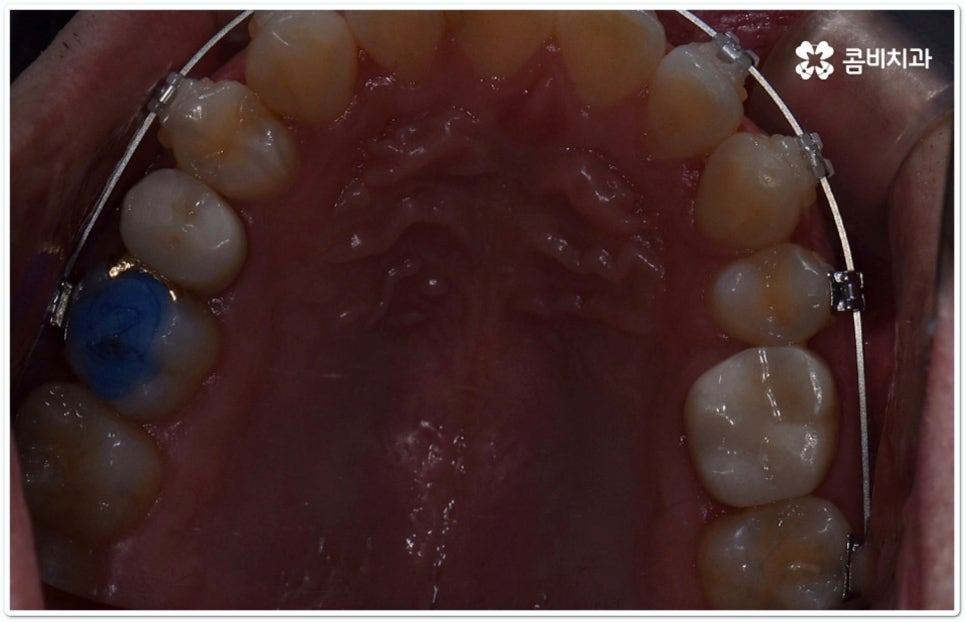

클리피씨교정 장치란 clippy-c 라는 단어 뜻에서 알 수 있듯이 클립이 달린 (clippy) 세라믹(ceramic) 브라켓 장치를 의미하고 있어요. 예전에 교정 장치에서 많이 쓰이던 방식은 고무줄 또는 미세철사를 이용하여 브라켓마다 각각 와이어를 묶어주는 것으로 날카롭게 잘린 철사 끝부분에 자칫 상처를 입을 수도 있고 한 달에 한 번 정도 치과에 내원하여 진행 상황에 따라 교정력을 조정하는 시간도 훨씬 더 많이 걸렸다고 할 수 있습니다.

이와는 다르게 클리피씨교정 장치는 자가결찰방식이라고 해서 각 브라켓에 여닫을 수 있는 특수한 클립(뚜껑)이 달려 있어 전체 와이어를 통과시켜 잡아주는 방식을 이용하기 때문에 겉면이 매끄럽고 진료 시간도 짧아지며 마찰로 빠져나가는 교정력을 줄여주어 좀 더 효율적으로 치아를 이동시킨다고 할 수 있어요. 즉 보다 적은 힘으로 지속적이고 부드러운 치아 이동을 가능하게 하므로 언급했던 것처럼 개인차가 있지만 전체 기간을 약 6개월 정도 단축시키고 치아가 이동할 때 느낄 수 있는 초기 통증도 감소시켜 줄 수 있는 거예요. 또한 치아 색상과 비슷한 세라믹 재질을 이용하기 때문에 음식을 먹거나 대화를 하는 등 입을 벌렸을 때 보일 수 있는 교정 장치가 그렇게 크게 눈에 띄지 않아 심미적으로도 뛰어나다는 장점을 가지고 있습니다.